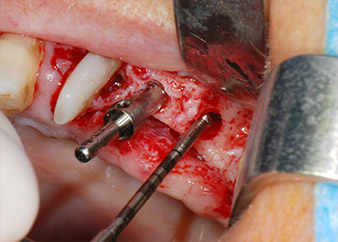

Prima di procedere al posizionamento dell'impianto, il tessuto infetto è stato rimosso dall'osso alveolare nel sito di impianto e attorno ai denti di appoggio con un attacco progettato per la sagomatura ossea e per la raccolta di frammenti ossei (Piezomed, attacco B5) (Figg. 6 e 7).

Le sedi di impianto sono state preparate in corrispondenza dei siti 25 e 26 con strumentazione rotante, utilizzando un manipolo contrangolo con una velocità di trasmissione 20:1 con motore potente di nuova generazione (Implantmed di W&H) (Fig. 8).

La preparazione finale vicino al seno mascellare è stata ancora una volta eseguita con uno strumento piezoelettrico (Piezomed, attacco S2).